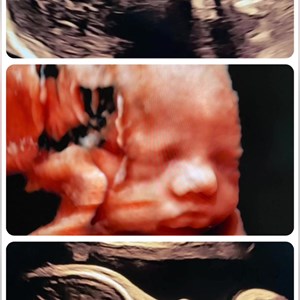

Dejlig lille suttelysten pige 3D scanning uge 33+1 med søde minder for hele familien 👀👶...

Sødeste lille pus ❣️#uge33 #3dlive #vægtscanning #babypics #hjertelyd #hjertelyd_scanning...